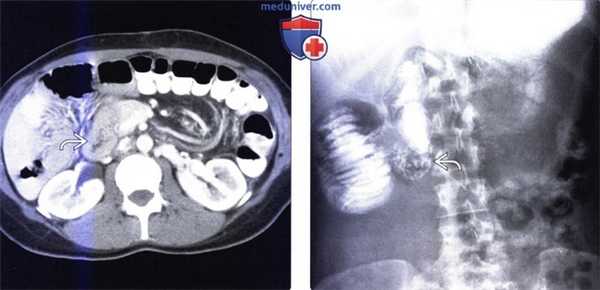

Мальротация кишечника (нонротация) у мужчины 39 лет.

(а, б) Тощая кишка — прямое продолжение двенадцатиперстной (стрелка, а), отсутствуют нормальные 3-й и 4-й сегменты двенадцатиперстной кишки, а также двенадцатиперстно-тощекишечный переход (звездочка, б).

(в, г) Петли тонкой кишки (прямые стрелки) лежат в левой половине брюшной полости, а ободочная кишка (изогнутые стрелки) — в правой половине. Заворот средней кишки у мальчика 11 лет.

(а) При КТ с контрастированием в аксиальной проекции выявлена транспозиция верхней брыжеечной артерии (указатель) и вены (стрелка).

(б, в) На более низких уровнях при КТ в аксиальной проекции выявлен симптом «водоворота» (стрелка), представляющий собой перекручивание верхней брыжеечной вены и ее ветвей, брыжеечного жира и петель кишки вокруг верхней брыжеечной артерии по часовой стрелке.

(г, д) На рентгенограммах выявлен симптом «штопора» — спиральная конфигурация 4-го отдела двенадцатиперстной кишки и проксимальной части тощей кишки.